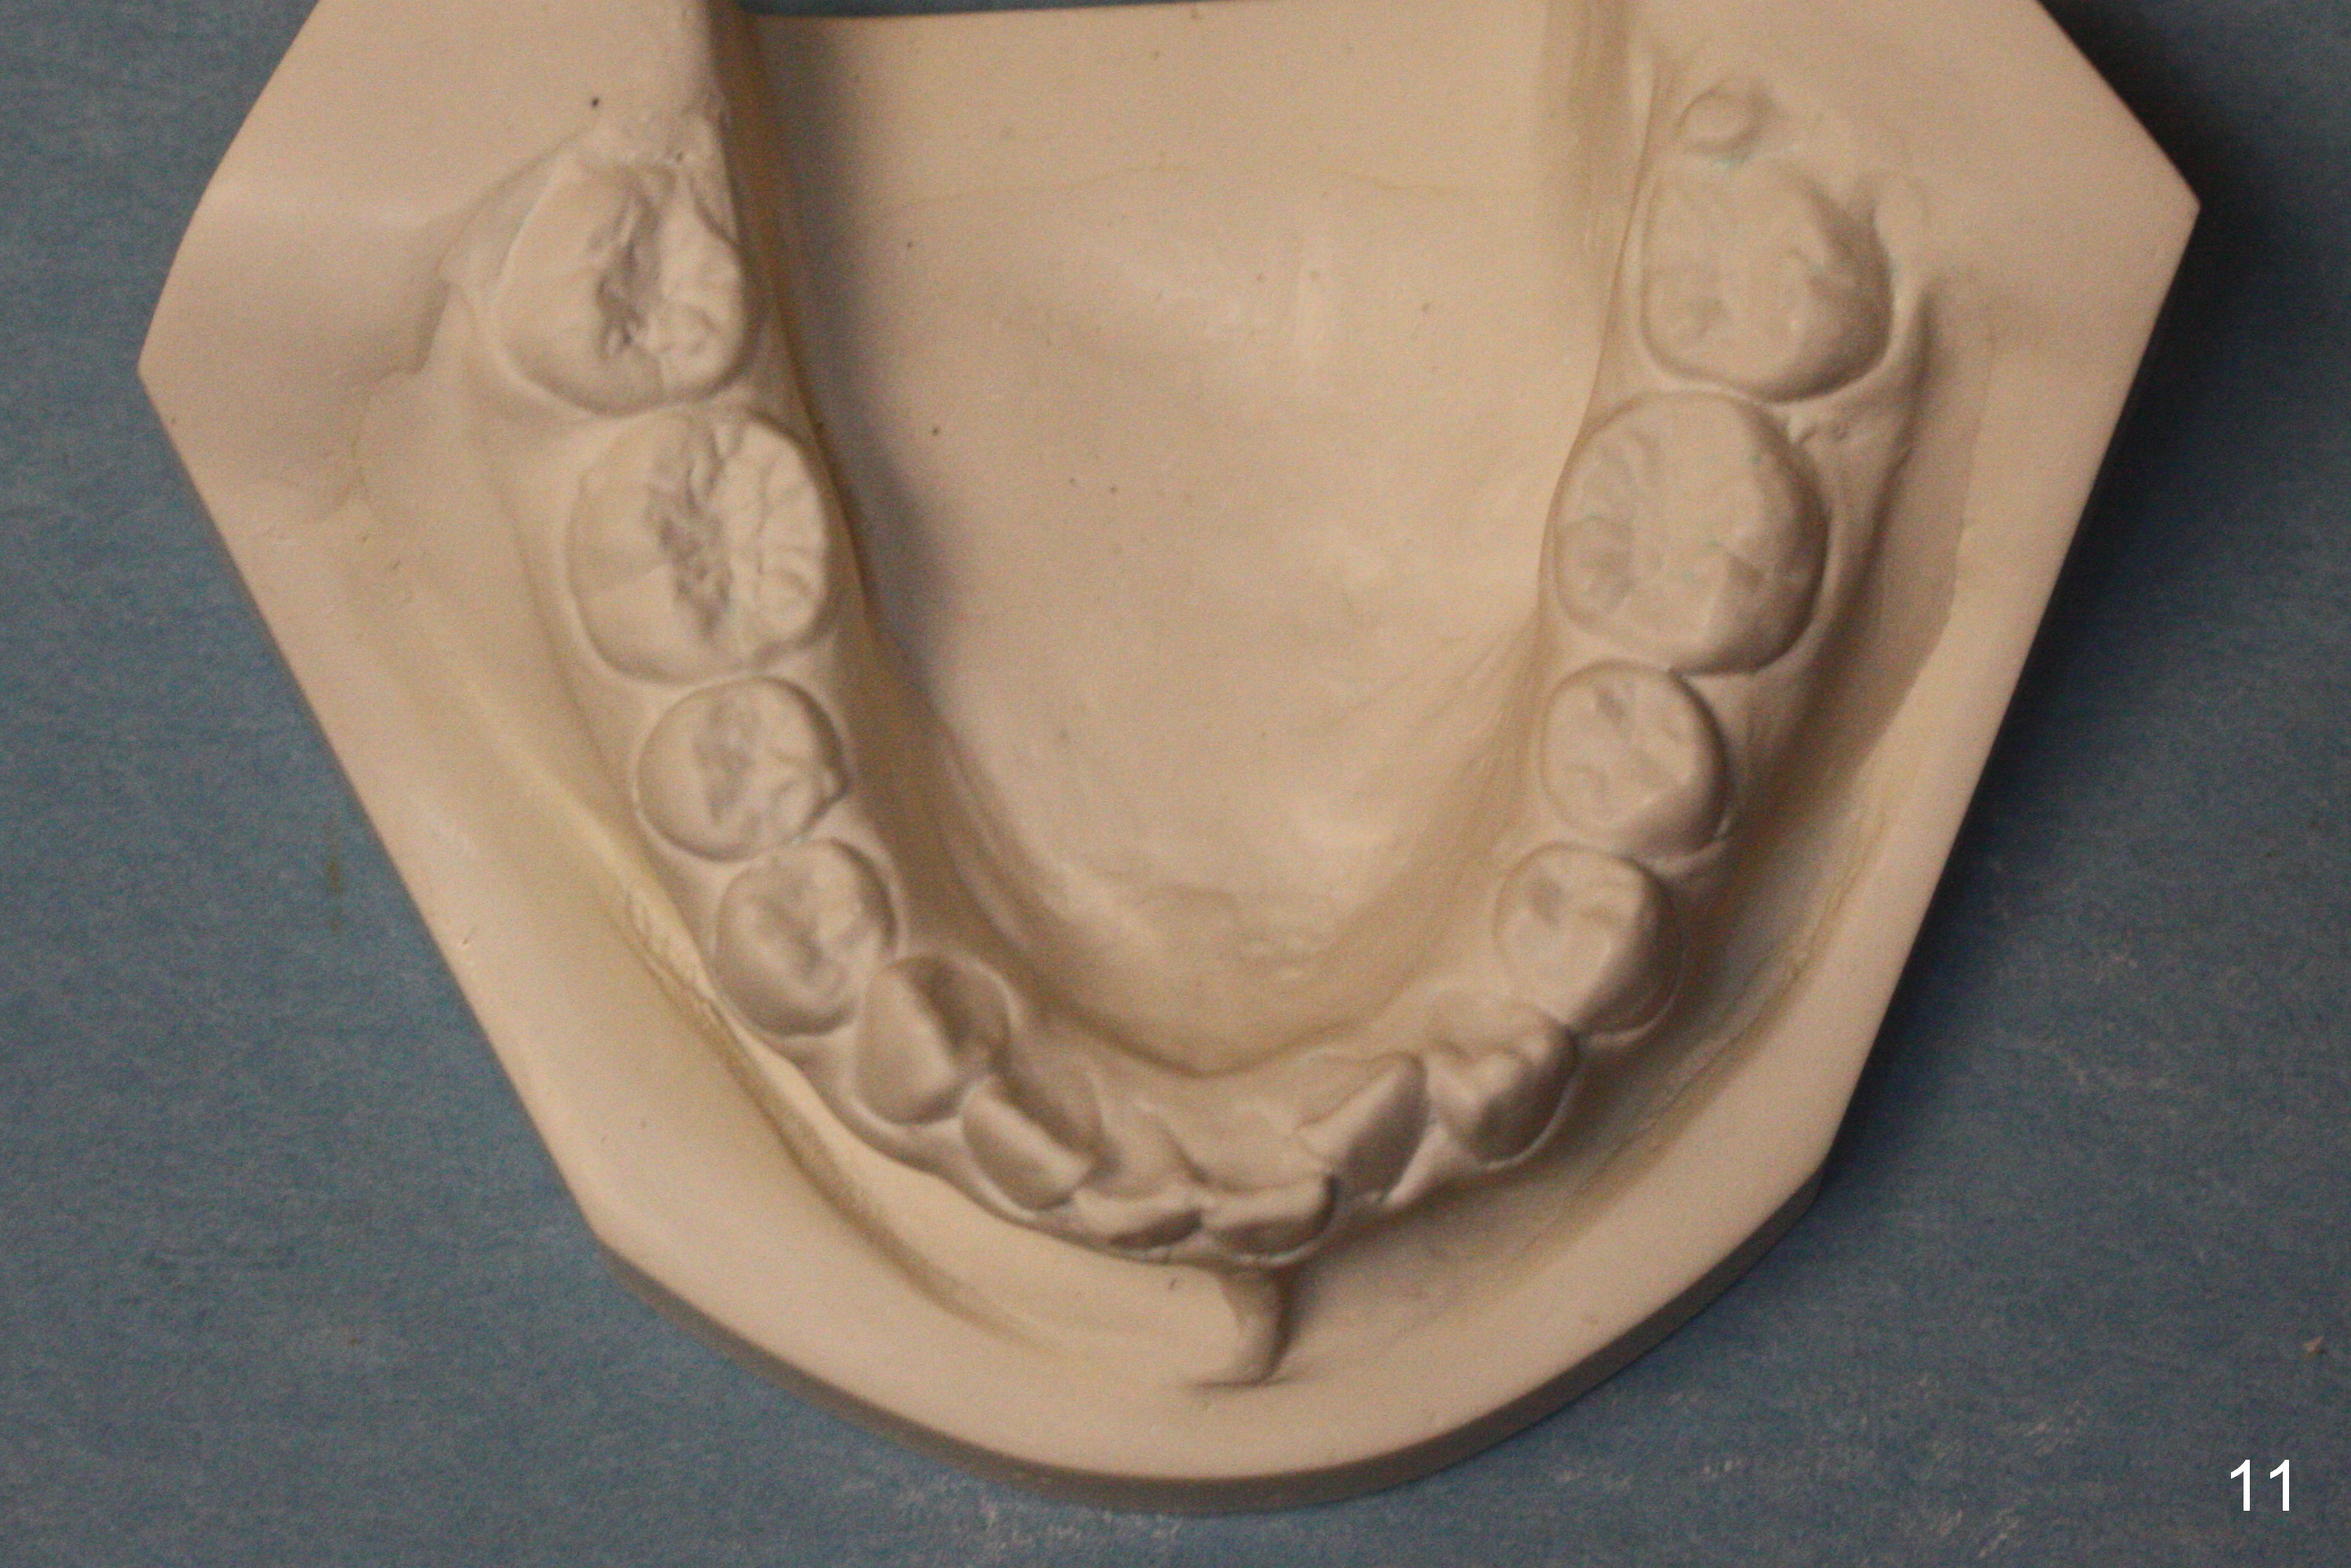

A 13-year-old girl denies mouth breath/nasal obstruction in spite of pointed narrow arches (Fig.10,11). When she is relaxed, the lips remain unclosed (Fig.1). There is lip strain when they try to close (Fig.2). When the patient is smiling, the upper central incisors have extra exposure (Fig.3). Differential bracket placement between U1 and U3 (4 vs. 5 mm from the incisal edge) should be able to correct the exposure. Profile views show the mild lip protrusion (Fig.4,5). Class II elastic retraction when arch wires reach 18 ss may be able to move the lower arch forward (Fig.6 arrow) and/or move the upper one backward (take care of Class II malocclusion (Fig.8,10) and lip profile).

Microdontia at U2s contributes to Class II malposition of U3s (Fig.7,9). No brackets are placed in U2s initially so that open coil springs can be placed between U2 and 3 to increase space. Composite veneers are to be fabricated near the end of orthodontic treatment, whereas porcelain veneers are going to be placed when she grows beyond puberty. Constantly encourage the patient for better oral hygiene before, during and after orthodontic treatment (Fig.8,9). Without extraction, the facial profile remains convex postop.